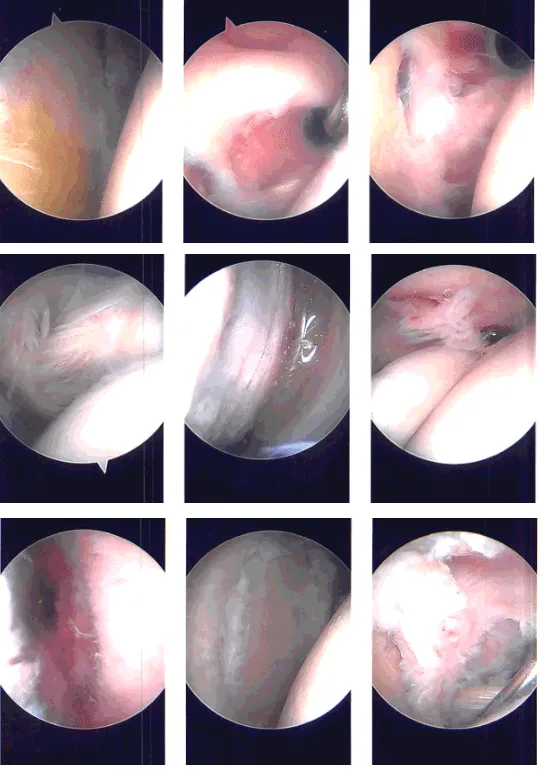

Arthroscope was entered and examination of the glenohumeral joint showed degeneration of the glenoid labrum with tear of the superior labrum and biceps anchor. There was tearing of the subscapularis muscle as well as supraspinatus on the articular side.

Shaver was used for debridement of the rotator cuff. Straight biter was used to cut the biceps and glenoid labrum was debrided using a shaver. Rest of the examination of the shoulder joint was normal. All the pictures were saved.

The arthroscope was entered into the subacromial space, where subacromial bursitis was present. The subacromial bursitis was debrided using a shaver through an anteromedial portal. A lateral portal was made. The scope was entered through the lateral portal and further debridement was done.

Acromioplasty was performed using a thermal wand followed by a shaver. AC arthritis was seen. Distal clavicular excision was performed using the thermal wand and burr. Rotator cuff was examined and found to be intact on the bursal side. Pictures were taken and saved.

Intraoperative Arthroscopy Images